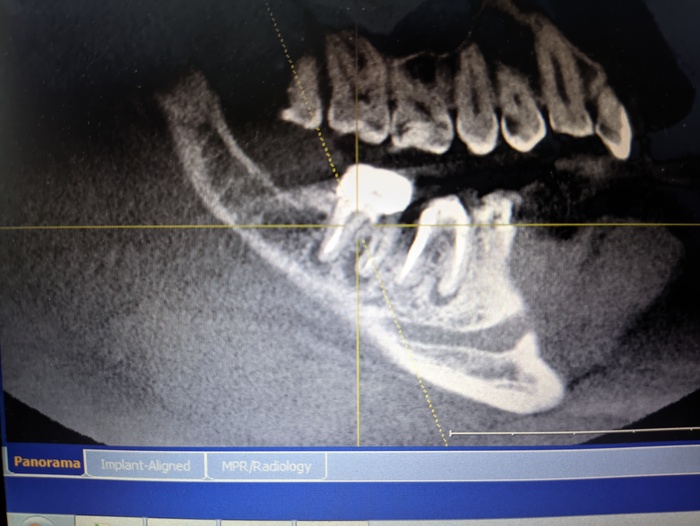

Весной 2021 лечил острый пульпит на 47 зубе, лечили каналы и депульпировали. Осенью поставил коронки на 45-47. В июле этого года сделал кт и врач сказал периодонтит и убыль кости на 46 и особенно на 47. Так понимаю 47 очень сложно вылечить будет. В клинике сказали, если не удастся вылечить, то только удалять. Имею ли я право по закону, если придется удалить 47 зуб, поставить в другой клинике имплант и потребовать с первой клиники компенсацию стоимости его установки ? Как правильно поступить?